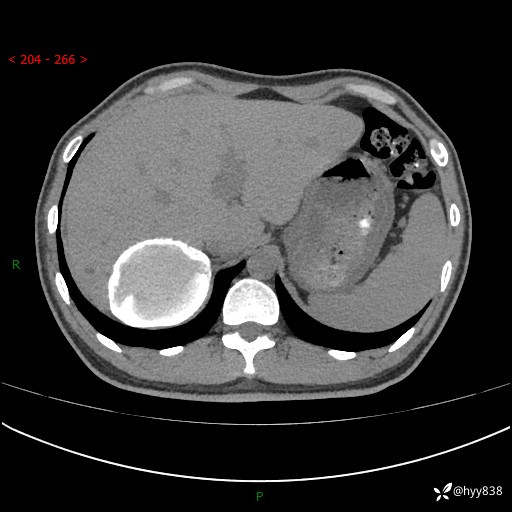

性别:男

年龄:50岁

简要病史:夜尿增多半月,发现肾功能异常1天,超声发现腹膜后占位

腹部CT平扫+增强